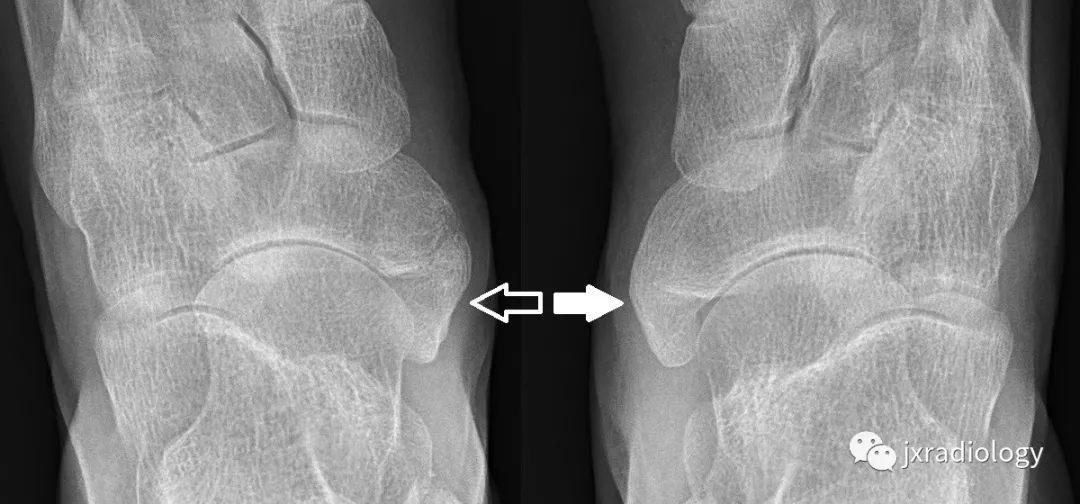

![左足舟骨病变,您考虑是啥? [病例帖]](https://imgs.wantubizhi.com/img/735A5D1F980B52A636CC46F12F2D1A737C2A898C797E84FF4D8C25186082B074081370FAFF35C777320835A8D99FF6C1F1D0BE88AC6C4F0E4B27E0BF24E02C066DE52B3FBEA72DF757BEA4C48533A6B9FD44C1E8394CF96D1BD42B83A6EB88B7) - 左足舟骨病变,您考虑是啥? [病例帖]图片尺寸1691x2000